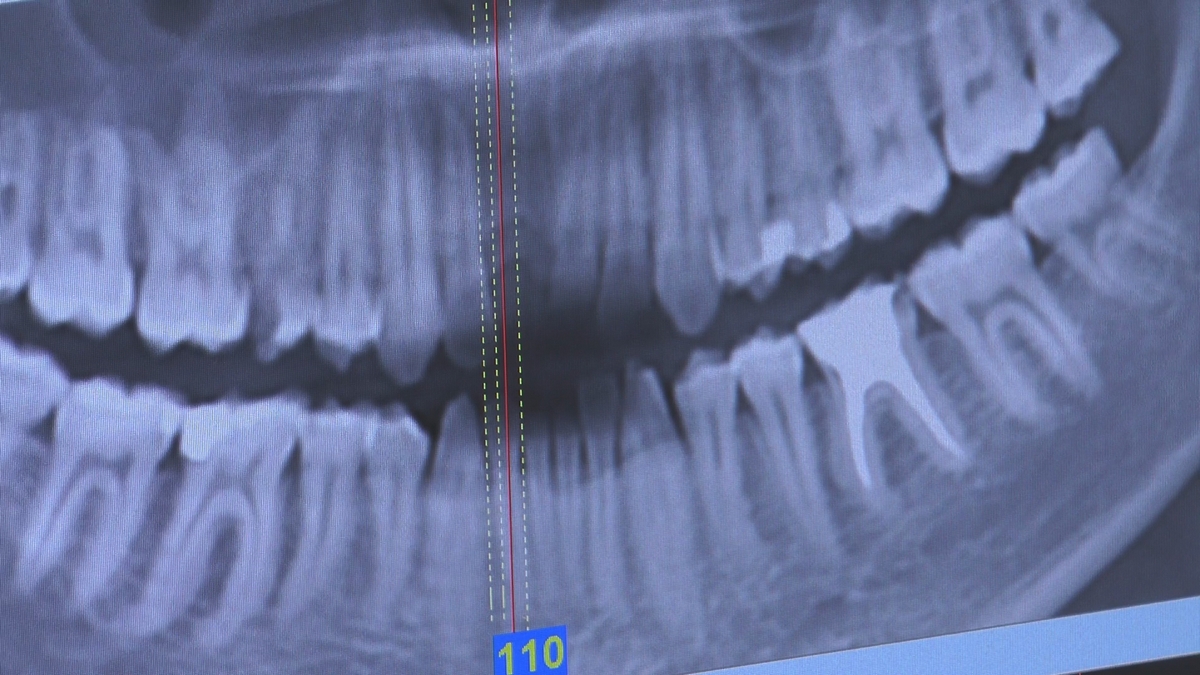

W trakcje dwóch dni zabiegowych, piątek i sobota, 5 i 6 października 2018 roku, lekarze uczestniczący w 6 Sesji VI Sezonu, wykonali wiele zabiegów o wysokim stopniu trudności. Przeprowadzili je pod kierunkiem Mentorów Instytutu Vivadental – dr n.med. Violetty Szycik, dr n.med. Magdaleny Kisłowskiej-Syryczyńskiej oraz dr Małgorzaty Piotrowskiej.

Wprowadziliśmy łącznie 25 implantów w tym wykonaliśmy:

dwa zabiegi All- on -4 / jeden w szczęce, jeden w żuchwie/ z usunięciem zębów i natychmiastową implantacją oraz natychmiastową odbudową protetyczną